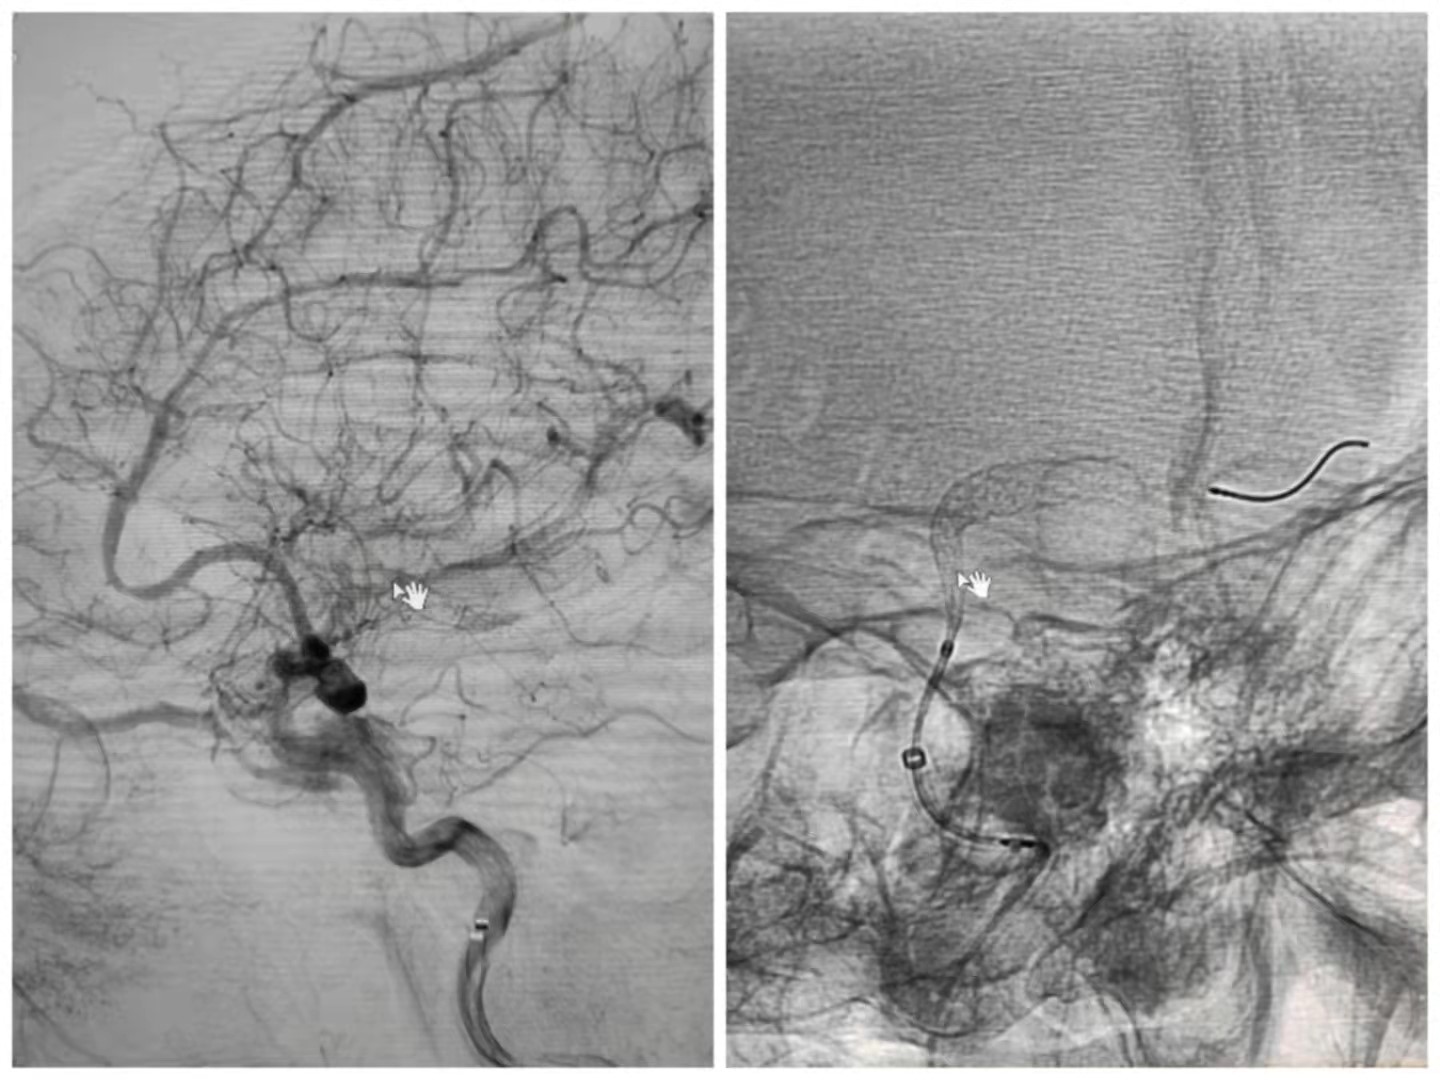

患者是一名64岁女性,因头痛在当地旗医院查CTA诊断为左侧后交通段宽颈动脉瘤,随后到我院神经外科进行治疗。颅内动脉瘤被称为颅内不定时炸弹,是常见的颅内血管疾病,严重威胁人类的生命健康。传统的治疗方法对于复杂的颅内动脉瘤(如巨大动脉瘤、宽颈动脉瘤及血泡样动脉瘤)治疗难度大、风险高且易复发。针对病人的情况,神经外科组织术前讨论,最终决定为病人实施血流导向装置(密网支架)植入技术,邀请宣武医院叶明主任医师指导手术,我院神经外科副主任医师呼和巴特尔实施手术,手术过程顺利,术后患者意识清醒,无神经功能障碍,造影显示动脉瘤内造影剂明显滞留,身体恢复较好,活动自如。